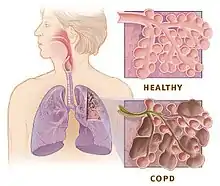

For the respiratory system, the LTF facilitated by intermittent hypoxia aids in increasing phrenic motor nerve output. This has been shown to help people with obstructive sleep apnea[17] and COPD.[18] The ability to increase muscle activity, specifically for walking, has also been demonstrated in both rats[16] and humans[19] after spinal cord injury.